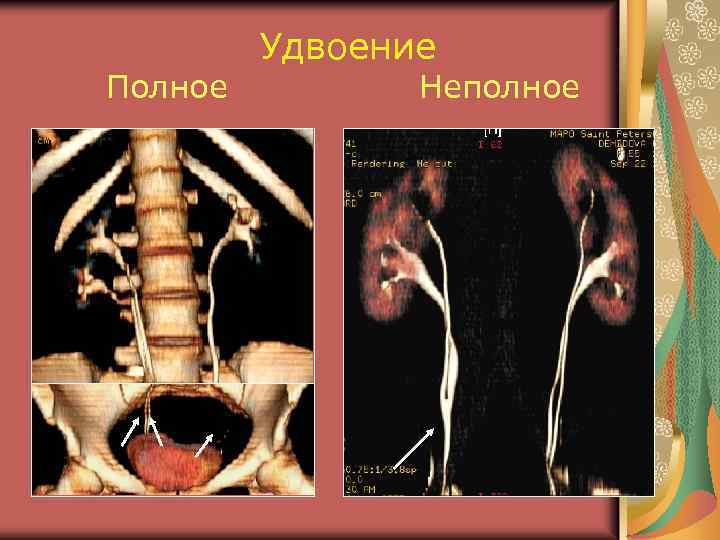

Полное Удвоение Неполное